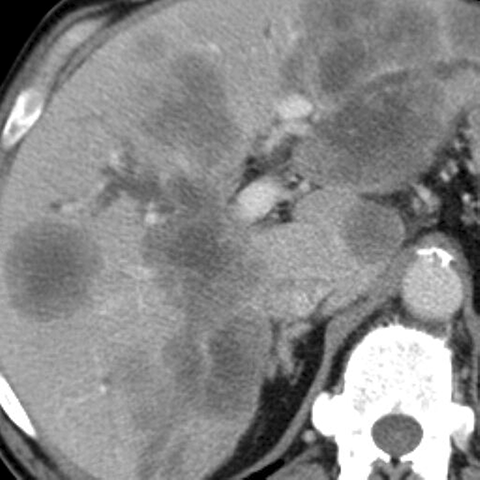

Liver metastases, CT ( axial ) [2 of 3]